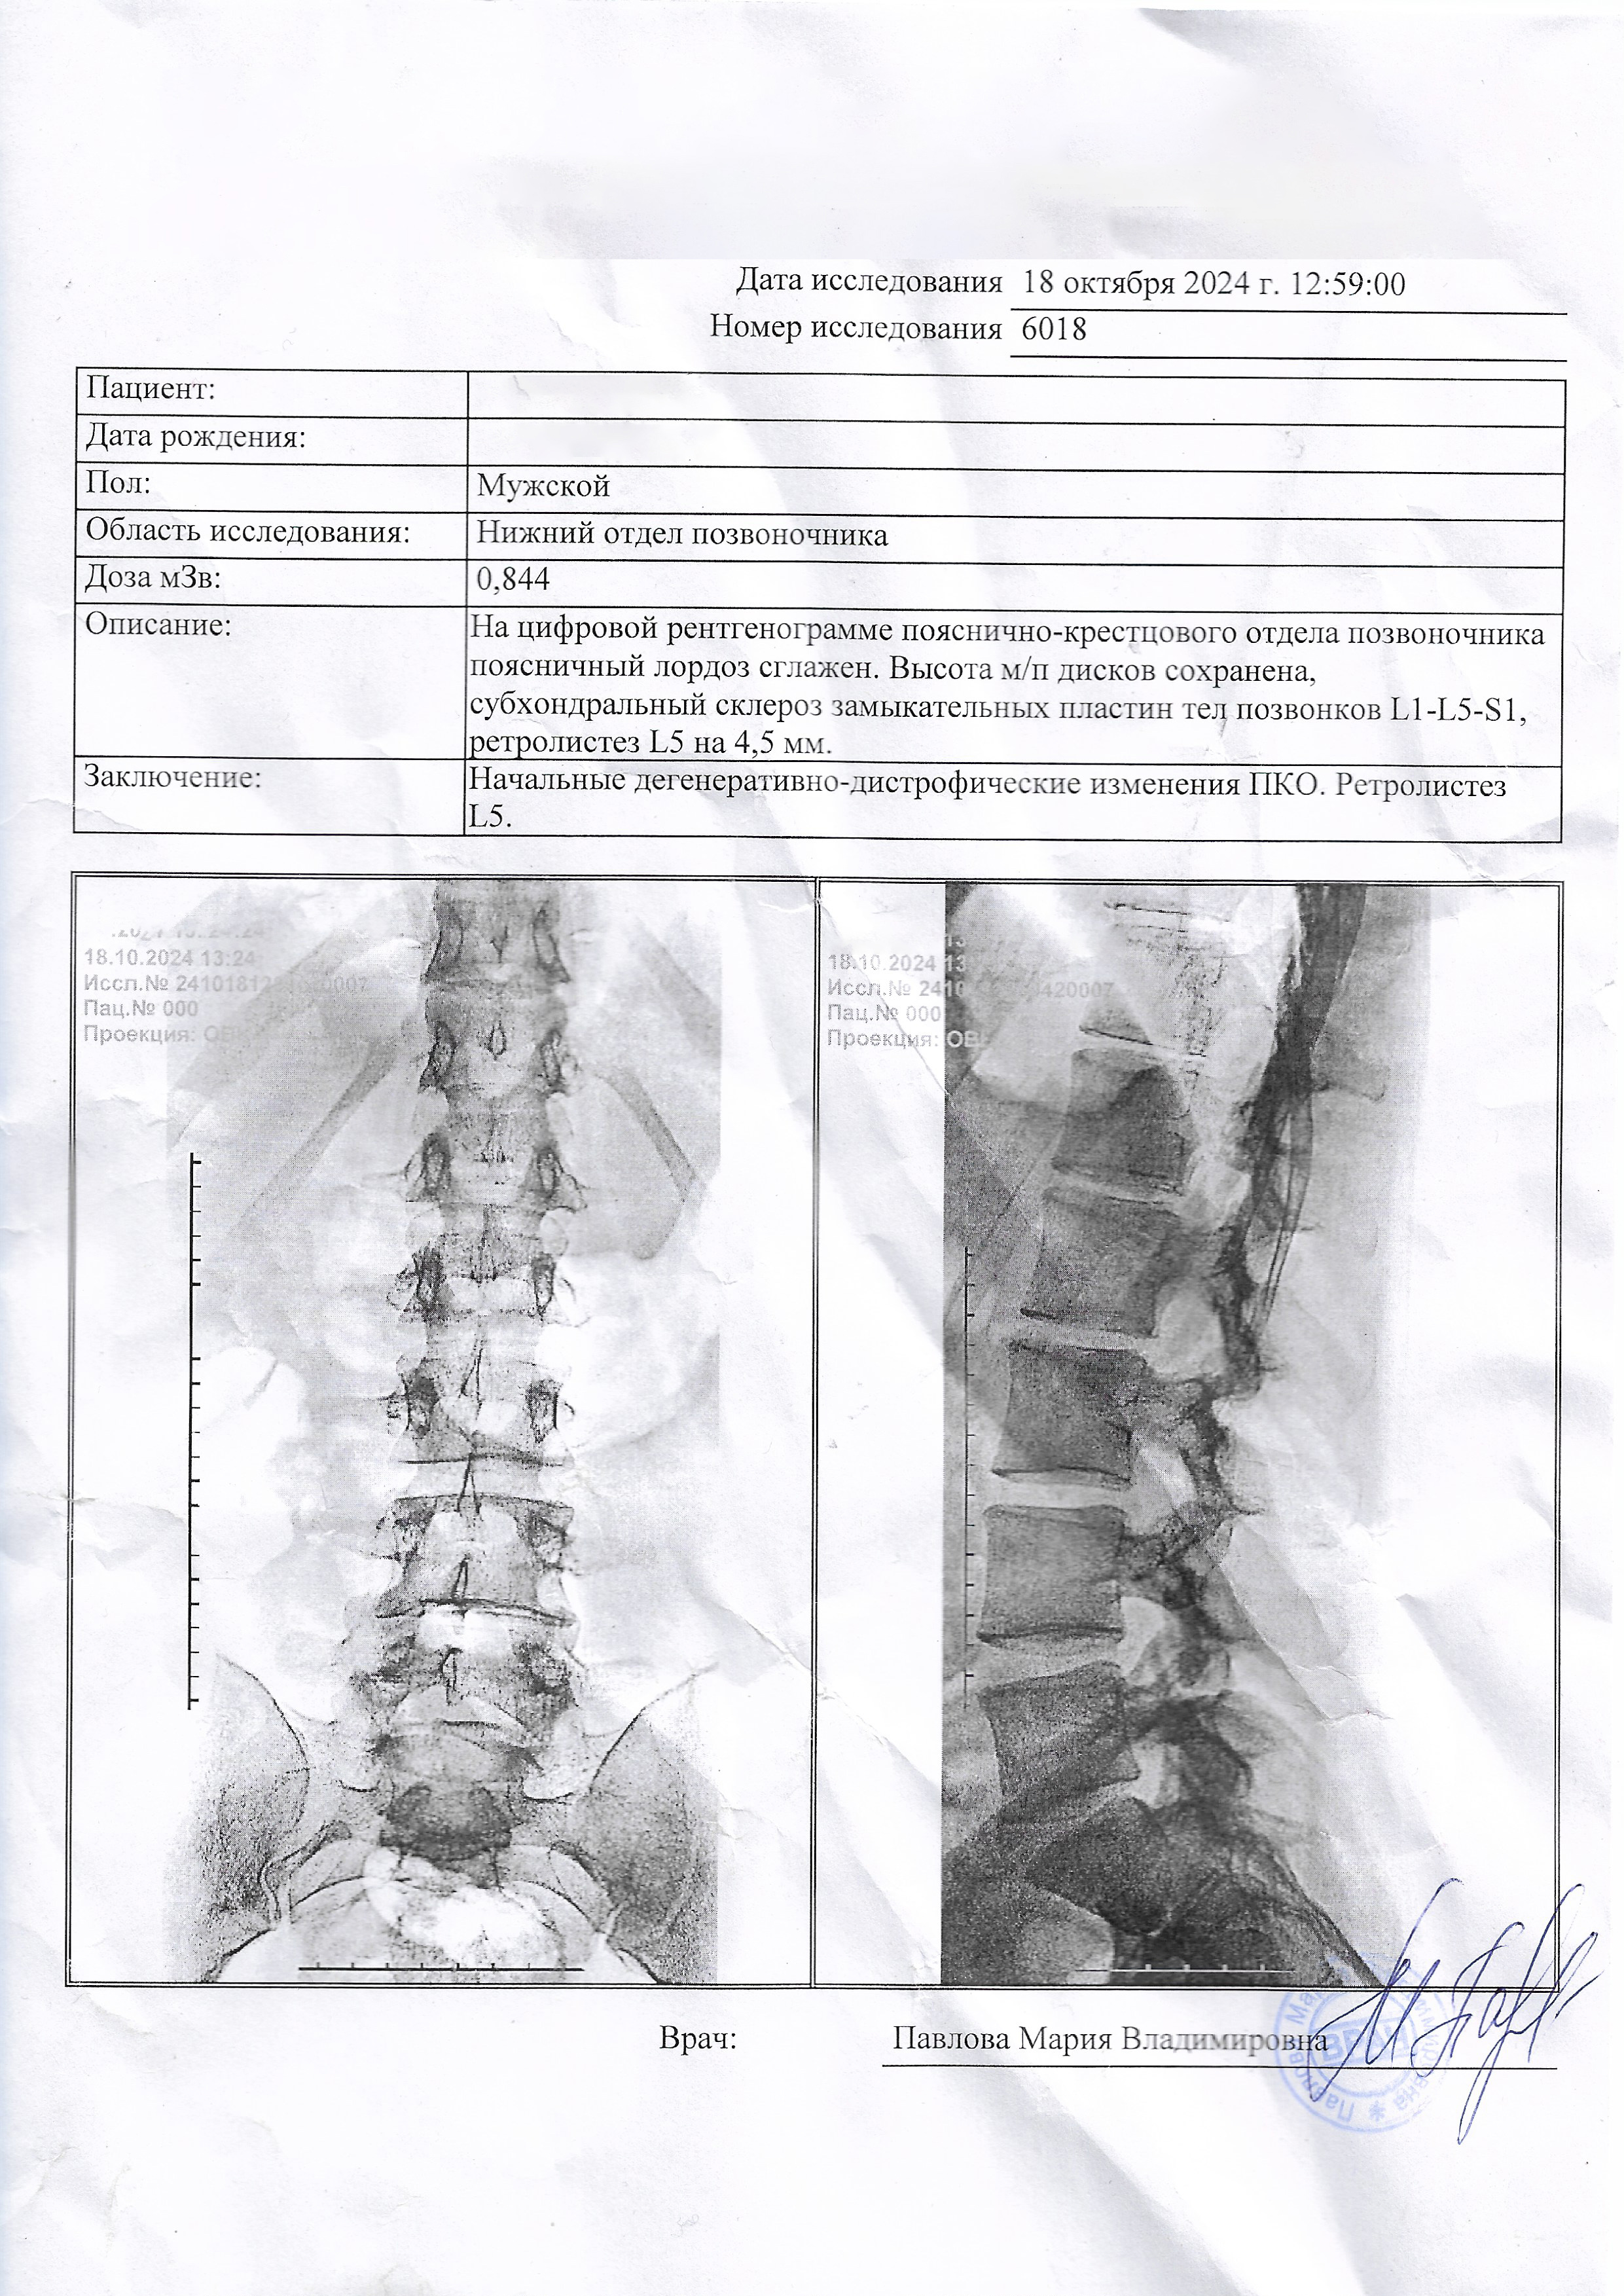

На базе прикреплённых документов, мне кажется, сложно будет парировать в военкомате насчёт моих дефектов спины